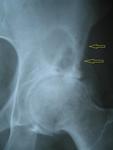

КТ, безусловно, необходима. Возможно, изменения различного характера — более крупное и овальное образование с тонким склеротическим ободком — это киста. А мелкие формирования, располагающиеся рядом, могут быть метастазами? Также на снимке виден участок остеосклероза в левой лонной кости.

Дефартроз, однако, признаков некроза головки не нахожу. В теле подвздошной кости видно многокамерное, окруженное склеротическим ободком кистовидное просветление с признаками периостита на этом уровне. (В его этиологии мне трудно разобраться)

Дефартроз, однако, я не вижу признаков некроза головки. В области подвздошной кости отчетливо видно многокамерное просветление, окруженное склеротическим ободком, с признаками периостита на аналогичном уровне. (Про его этиологию мне трудновато сделать вывод)

Простите, не могли бы Вы показать на снимке признаки периостита?

Извините, не могли бы Вы показать на снимке признаки периостита? Неровности, нечеткие контуры. Приложения: